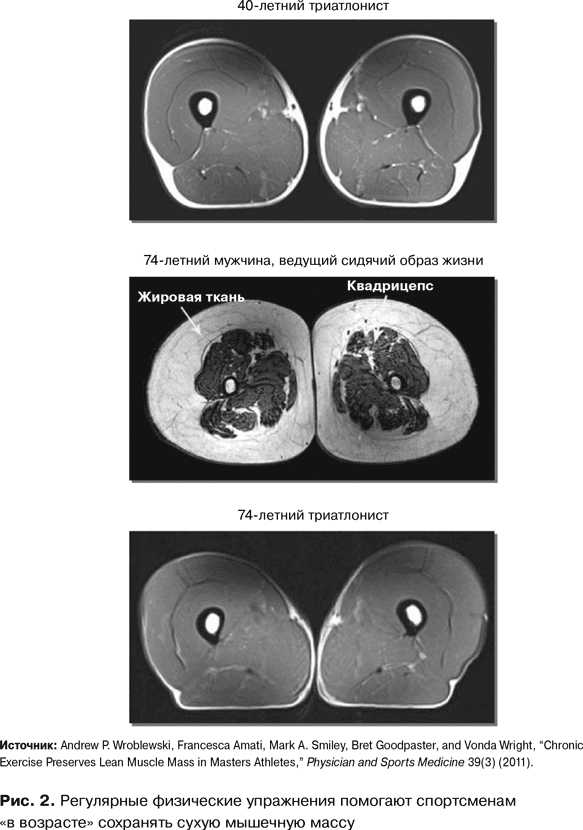

Что же происходит с мышцами, если вы регулярно и активно двигаетесь? Мы с коллегами решили ответить на этот вопрос, понаблюдав за немолодыми спортсменами-любителями, тренирующимися четыре-пять раз в неделю{8}. Благодаря снимкам МРТ я смогла отследить изменения в объемах сухой мышечной массы. Результат меня потряс.

Постоянная подвижность сохраняет сухую мышечную массу, предотвращает заплывание мышц жиром и потерю мышечной силы. Источник молодости существует, а волшебный эликсир – это подвижность! Но, как говорится, лучше один раз увидеть.

На рис. 2 представлен снимок бедра 40-летнего триатлониста. Похоже на кусок нежирной говядины. Мышцы в превосходном состоянии, мышца жиром не заплыла, подкожного жира практически нет. Далее мы видим снимок бедра 74-летнего мужчины, ведущего сидячий образ жизни. Совсем другая картина, правда? Мышцы развиты слабо, количество подкожного жира значительно, жир проник и в мышцы. Это скорее жирный ростбиф, чем постная говядина. А теперь взгляните на следующий снимок. Кульминационный момент. Мы видим бедро физически активного 70-летнего мужчины, триатлониста. Перед нами снова будто кусок нежирной говядины – отличное состояние мышц, совсем мало жира, что внутри, что вокруг. И – в качестве бонуса – видно, что квадрицепсы человека, живущего активной жизнью, с годами не теряют силы. В ходе моего исследования ни в одной возрастной группе до 60 лет не наблюдалось никакого статистически значимого расхождения в силе, а затем – никаких дополнительных различий вплоть до последней, 80-летней возрастной группы.